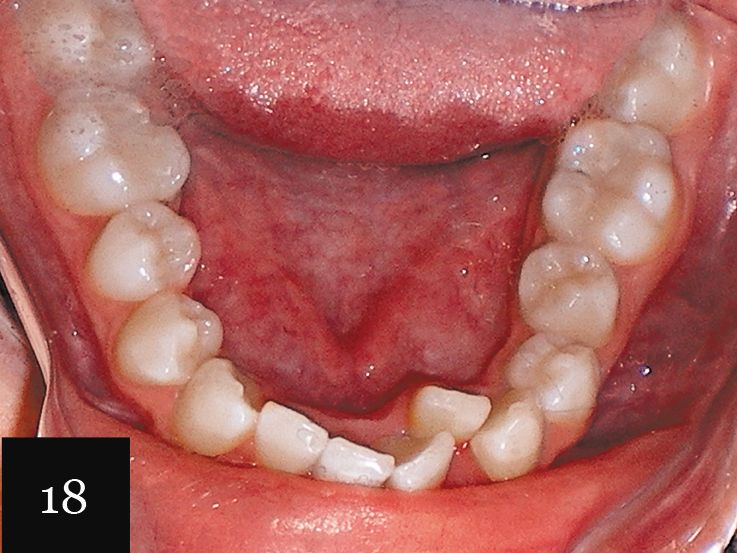

This case was performed on a patient in her late teens who presented with a very deep bite and severe crowding, as seen in Figs. 15-17.

The patient had consulted with multiple dentists who informed her that the lower lateral incisor would have to be extracted and that she was not a candidate for Invisalign. However, with an accurate impression we were indeed able to successfully treat this case with Invisalign, first using a series of 27 aligners, and then following up with an additional impression and eight more aligners for refinement (Figs. 18-20).